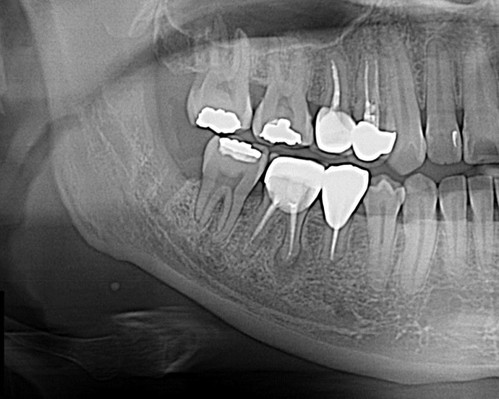

사랑니 뿌리가 신경관과 근접

교정력을 주어 열심히 당기기 한 달 별다른 위치변화가 보이지 않아서 좀 답답하다...

그리고 한 달이 더 흐른 후 x-ray를 확인하며 너무 행복했다.. 노력이 헛되지 않았으니

이 사랑니가 누워있지 않고 서있어서 오히려 교정력을 주기가 더 어려웠다.